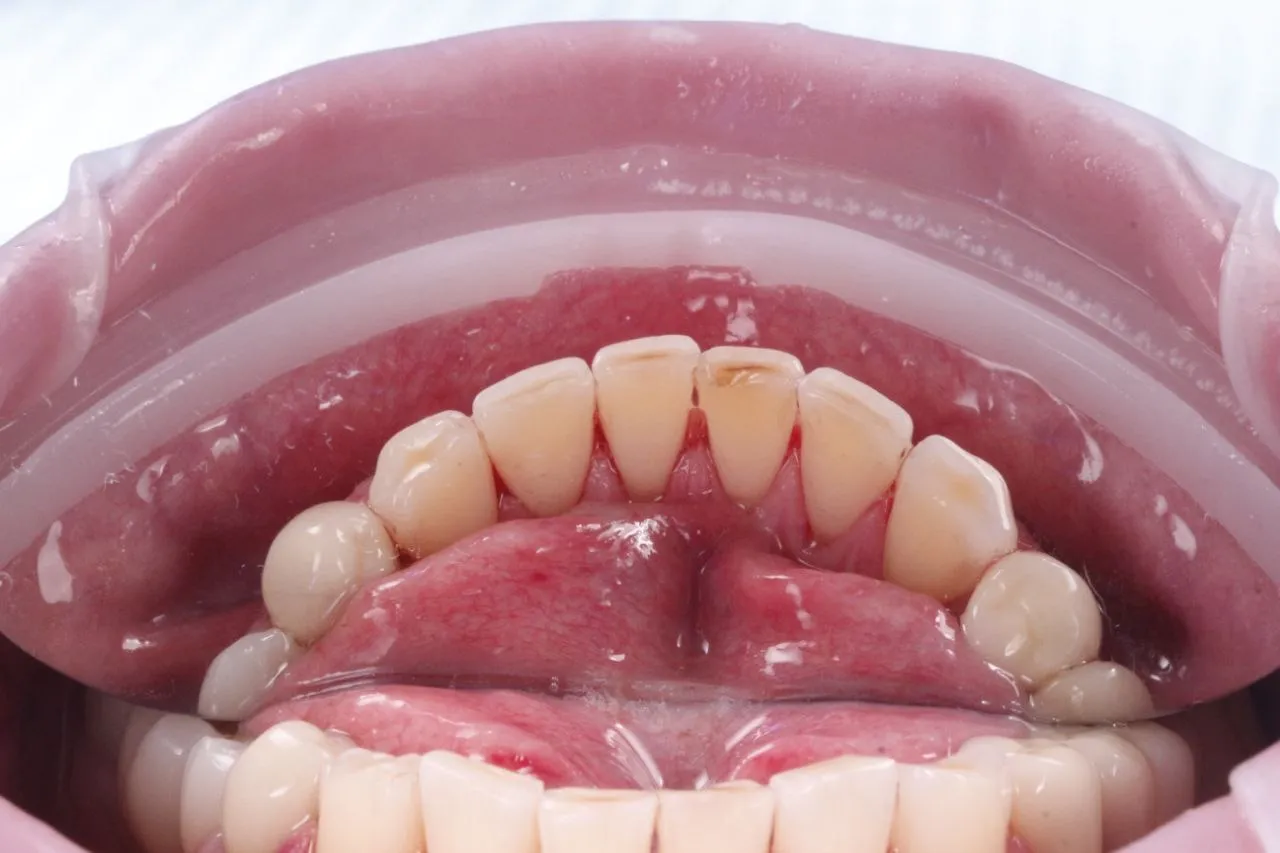

Професійна гігієна порожнини рота